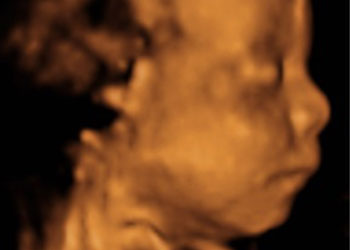

Ejemplos de ecografías del embarazo